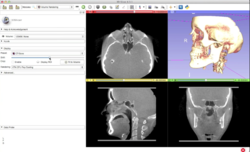

DICOM

• The DICOM and Slicer tutorial provides an introduction to the DICOM standard and shows how to load and visualize DICOM datasets in 3D Slicer version 5.0.

• Author: Sonia Pujol, Ph.D.

• Modules: DICOM, Volumes

• Based on: 3D Slicer version 5.0/4.11

• The 3D Slicer DICOM Tutorial Data contains a torso-CT and a breast MRI.

• The 3D Visualization of DICOM images course guides through 3D data loading and visualization of DICOM images for Radiology Applications in Slicer4.

• Author: Sonia Pujol, Ph.D., Kitt Shaffer, M.D., Ph.D., Ron Kikinis, M.D.

• Audience: Radiologists and users of Slicer who need a more comprehensive overview over Slicer4 visualization capabilities.

• Modules: DICOM, Volumes, Volume Rendering, Models.

• Based on: 3D Slicer version 4.8

• Compatible with 3D Slicer version 4.10

• The 3DVisualizationDICOM_part1 and 3DVisualizationDICOM_part2 datasets contain a series of MR and CT scans, and 3D models of the brain, lung and liver.